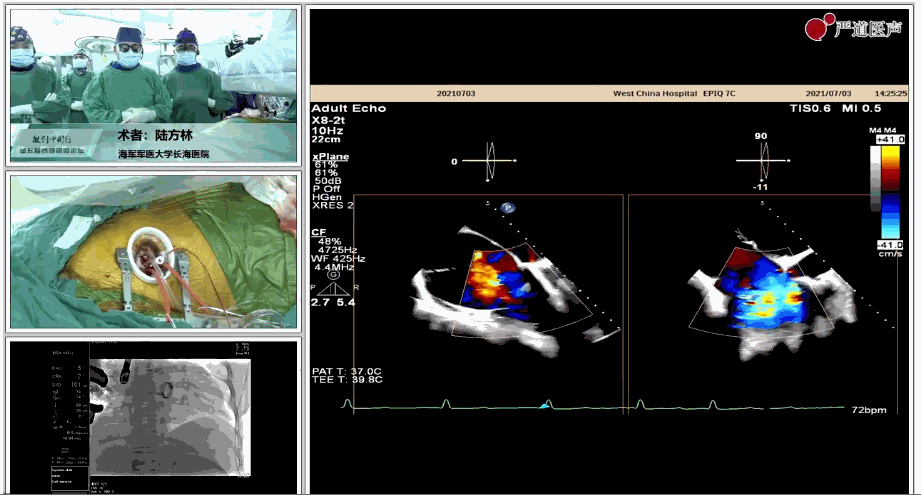

7月3日下午,海軍軍醫(yī)大學(xué)附屬上海長(zhǎng)海醫(yī)院心血管外科徐志云、陸方林團(tuán)隊(duì)在論壇中分享了經(jīng)導(dǎo)管三尖瓣置換術(shù)(LuX-Valve®)的手術(shù)直播演示。線(xiàn)下會(huì)議由陶涼教授、潘文志教授、喬晨暉教授共同參與討論和臨床分享。

陸方林教授分享的是一例極重度三尖瓣返流的患者采用健世科技(LuX-Valve®)經(jīng)導(dǎo)管三尖瓣置換系統(tǒng)進(jìn)行的手術(shù)直播演示。此例患者為69歲女性,入院前17年行二尖瓣機(jī)械瓣置換術(shù),術(shù)后長(zhǎng)期服用華法林抗凝,既往“2型糖尿病”病史5年,“雙下肢水腫”3年。3個(gè)月前患者出現(xiàn)腹脹、雙下肢水腫,伴活動(dòng)后暈厥,伴黃疽、皮膚濕癢、牙齦出血,癥狀持續(xù)加重,遂入院治療。入院后行心臟CT、心臟超聲檢查,提示:“三尖瓣關(guān)閉不全(極重度),二尖瓣置換術(shù)后,心功能III級(jí)”。徐志云、陸方林微創(chuàng)三尖瓣置換團(tuán)隊(duì)對(duì)該患者的病情進(jìn)行了充分的評(píng)估和討論。由于患者有開(kāi)胸二尖瓣置換手術(shù)史,且病史時(shí)間長(zhǎng),同時(shí)存在相關(guān)合并癥,傳統(tǒng)外科手術(shù)風(fēng)險(xiǎn)極高(STS評(píng)分:8.315%),最終決定采用三尖瓣LuX-Valve®瓣膜系統(tǒng)對(duì)患者進(jìn)行治療。

▲術(shù)中食道超聲顯示三尖瓣極重度返流